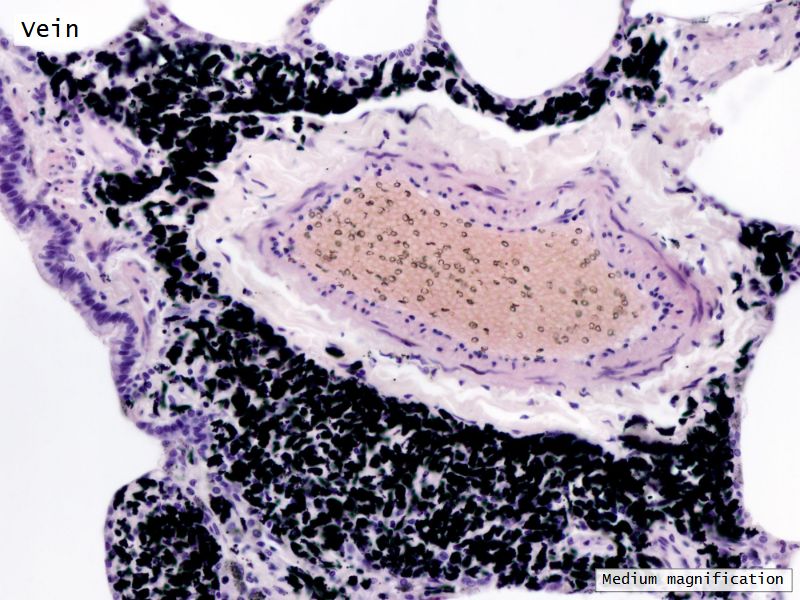

Fill in all the missing labels, and assess as you move through the slides. Answers on the down slide. It is important to do this using pen and paper, and not just glance through the images.